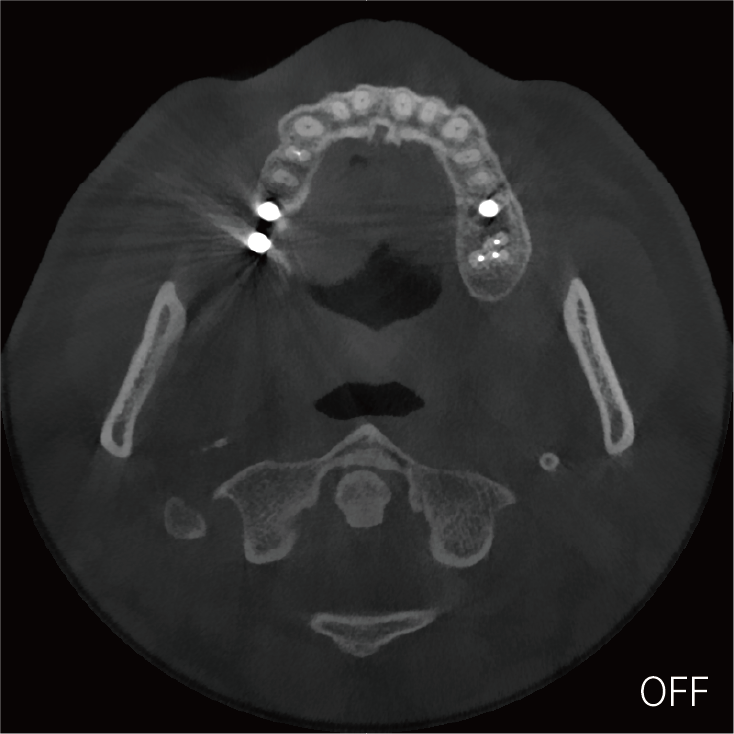

局部超清显示、 移动视野摄片

真人正侧位投影,实现CT成像区域无极可调

可根据临床需求任意调整成像区域大小实现局部超清三维显示

临床样片